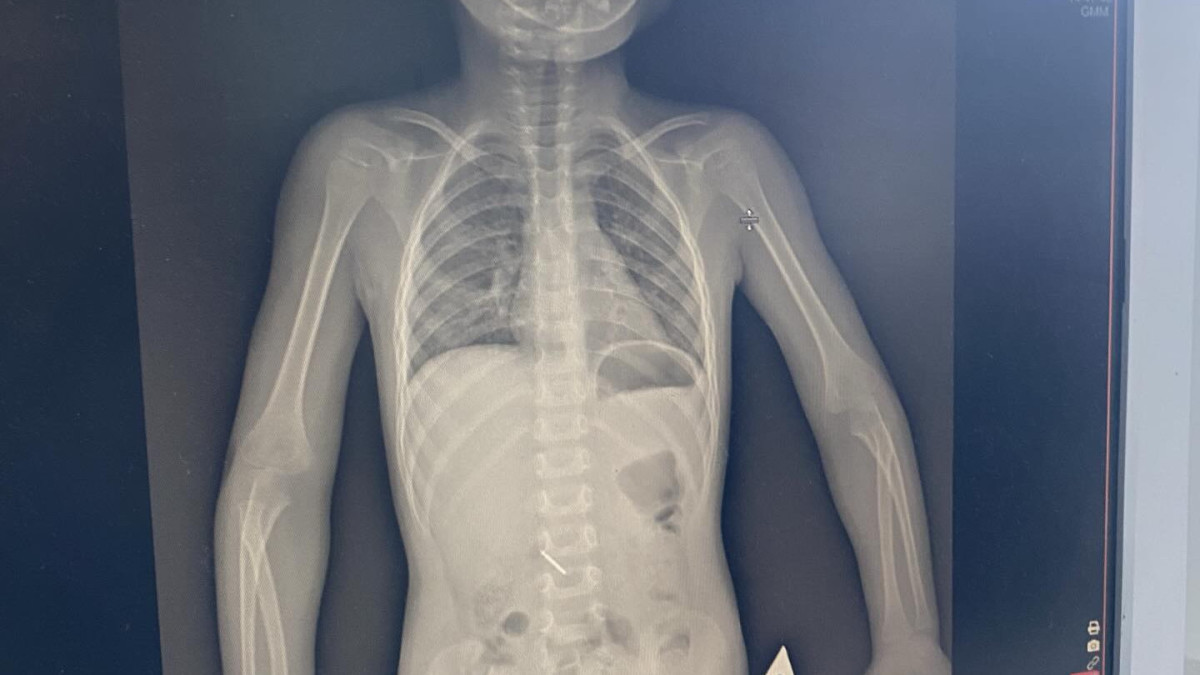

Көкшетауда жеке емханада қабылдау кезінде 3 жасар бала стоматологиялық құралды жұтып қойған. Бұл оқиға туралы баланың анасы Threads әлеуметтік желісінде жазды, деп хабарлайды BAQ.KZ тілшісі.

Оның айтуынша, тісін емдеу кезінде бала стоматологиялық бұрғыны (бор) жұтып қойған.

Бірнеше күн ішінде бала екі рет рентгенологиялық зерттеуден өтіп, хирург қарауында болған және оған ФГДС (фиброгастродуоденоскопия) процедурасы жасалған.

26 ақпандағы жағдай бойынша, бөгде зат әлі табиғи жолмен шықпаған. Анасының сөзіне қарағанда, емдеуші дәрігер жеке келіп кешірім сұрамаған, ал клиника басшылығы тек емдеу ақысын қайтаруды ұсынған.